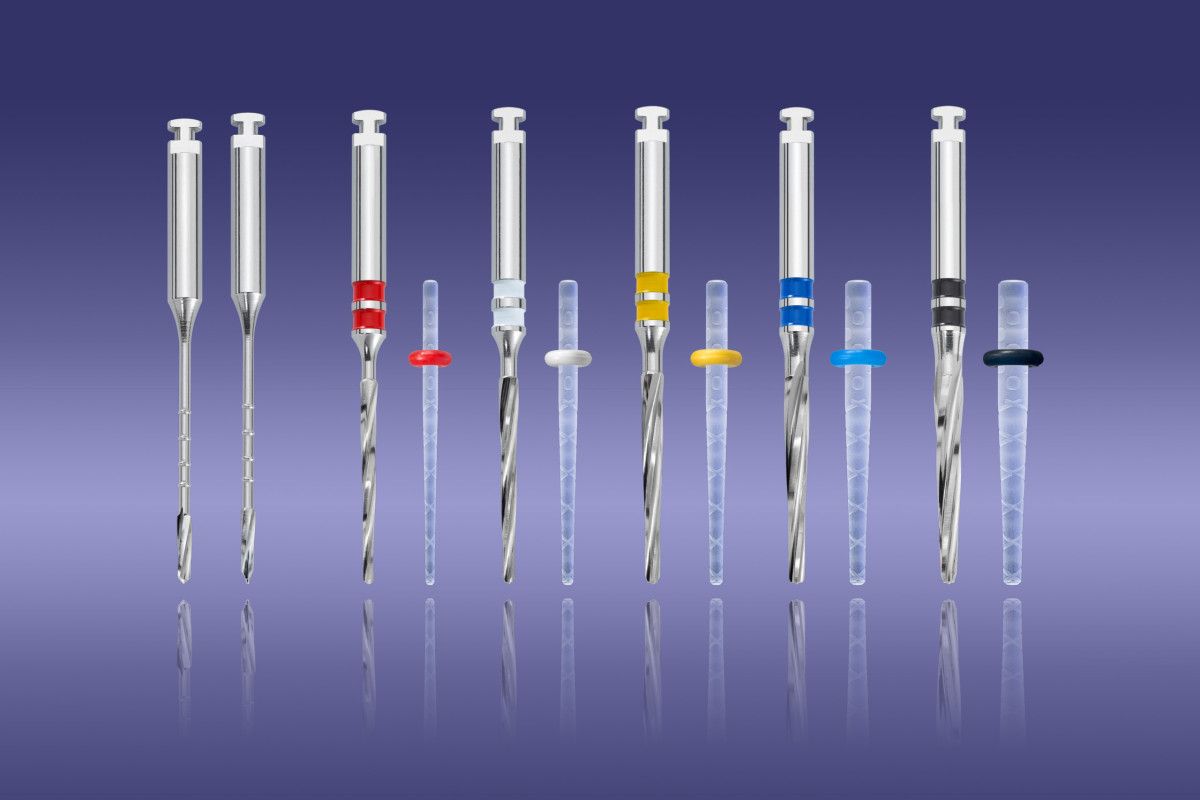

ContecPRO – Posts & Drills

Drills

1 x pilot drill with guiding tip

1 x pilot drill cutting tip

1 x calibration drill red

1 x calibration drill yellow

1 x calibration drill white

1 x calibration drill blue

1 x calibration drill black